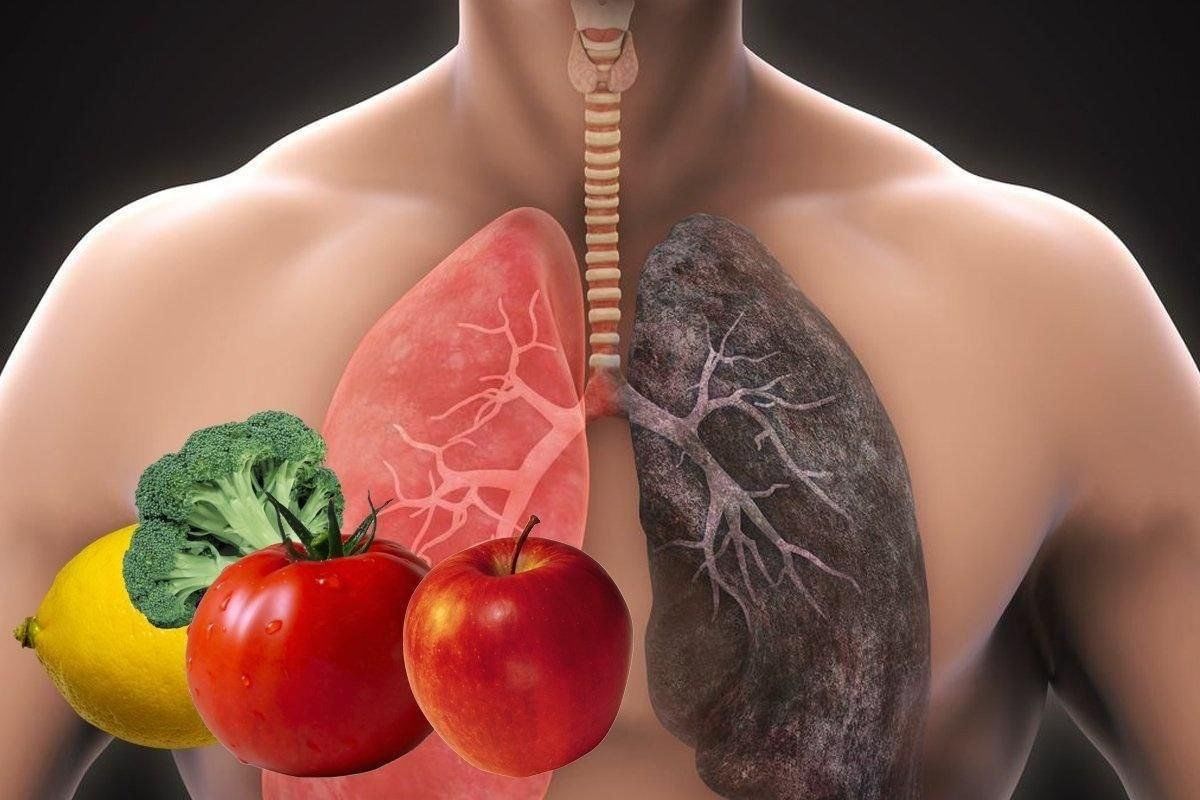

Таинство дыхания: глубокий взгляд на легкие человека в картинках

Раздел: Снимки-откровения